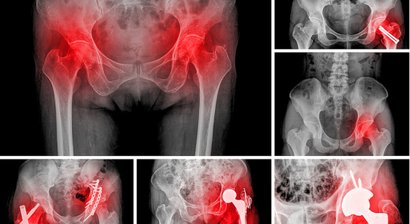

Hüftprothese

Die Hüftarthrose (Coxarthrose) ist ein häufig auftretendes Krankheitsbild, welches durch den allmählichen Verschleiß vom Hüftgelenk charakterisiert ist. Aufgrund von Umbauprozessen im Knorpelgewebe kommt es zu einer Störung im Knorpelstoffwechsel - der Gelenkknorpel ra...